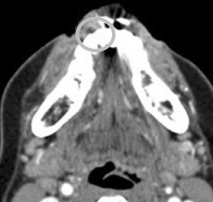

口内检查发现患者右下颌前磨牙颊侧前庭处可见一肿胀,约2*1.5cm大小,质韧,扪诊无疼痛。颈部及颌下淋巴结未见肿大。 全景片未见明显异常。 CT显示右下颌第一前磨牙处有一约2cm大小低密度肿块